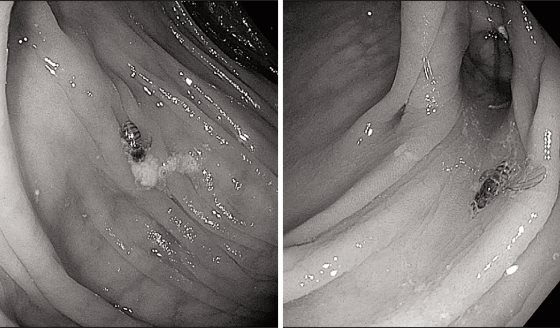

Tras una infección inicial, el VHS persiste de forma latente en las células nerviosas, a partir de las cuales puede reactivarse y causar herpes labial, herpes genital y queratitis (inflamación de los ojos). La publicación de este estudio en una revista científica confirma la tendencia investigadora sobre la capacidad de las terapias génicas para eliminar reservorios latentes del VHS (véase La Noticia del Día 30/09/2022). Además, incide también en la capacidad de reducir la cantidad de virus transmisibles liberados por los animales que han recibido dicha terapia y recoge la disminución del riesgo de problemas hepáticos y neurológicos registrados en las investigaciones previas.

La terapia génica es una forma experimental de tratamiento que utiliza la transferencia de genes a las células de un aminal o una persona para curar una enfermedad. En este estudio con ratones se han inyectado moléculas de edición genética que buscan el virus del herpes que se esconde en el cuerpo (concretamente, entre las células nerviosas, y al despertar provoca ampollas dolorosas en la piel).

El virus de entrega modificado en laboratorio contiene una enzima meganucleasa que, según han explicado los investigadores responsables del estudio, funciona como "tijeras moleculares". Al llegar al grupo de nervios en los que se esconde el herpes, se libera dicha enzima, que corta diversos segmentos del material genético viral inactivando al VHS. Posteriormente, los propios sistemas de reparación del cuerpo reconocen el ADN dañado como extraño y se deshacen de él.